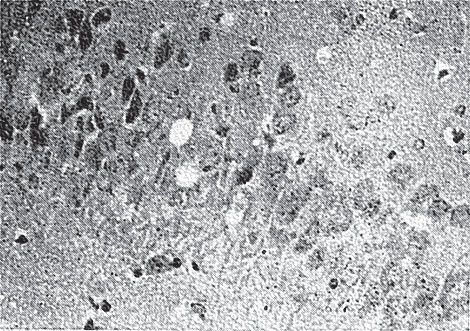

Для проверки этого предположения поставили специальный опыт «перекрестной подсадки»: от самки-вирусоносителя мышат сразу после рождения пересаживали к нормальной, здоровой (контрольной) самке и, наоборот, нормальных мышат (родившихся от контрольной самки) пересаживали к самке-вирусоносителю. Вне зависимости от кормящей матери вирус обнаруживали только в организме мышат, родившихся от самки-вирусоносителя. Следовательно, вертикальная передача вируса гриппа состоялась! Мало того, сотрудники нашей лаборатории М. С. Гордеева и Н. Б. Нефедова установили, что радиоактивно меченный вирус проходит через плаценту в организм плода буквально «как горячий нож сквозь талое сливочное масло». Но самая главная находка ждала нас впереди. Обнаружение у мышат, родившихся от самок-вирусоносителей, повышенных концентраций инфекционного вируса, да еще абсолютно во всех органах, конечно же, обескураживало. Что касается Е. П. Мирчинк, то ее удивление граничило с возмущением (как будто вирус просто не имел права на персистенцию в столь высоких титрах, да еще в столь широких масштабах). Не буду скрывать, полученные результаты смутили и автора этих строк. Во всем этом разобраться нам очень помогли факты, связанные с историей изучения вируса лимфоцитарного хориоменингита, с которыми мы с вами недавно познакомились (помните «призрачное благополучие»?). Наши мышата после рождения тоже выглядели внешне здоровыми и подвижными. Это благополучие настораживало (не было ли и оно призрачным?). Именно поэтому я попросил Е. П. Мирчинк отсадить таких мышат и понаблюдать за ними подольше. Отсаженные зверьки долгое время не вызывали сомнений в состоянии их здоровья. Но вот миновало три недели, и у некоторых из них начали появляться признаки… отставания в росте и массе тела, становившиеся все заметнее. Так, их братья и сестры (они называются сибсы) спустя два месяца весили по 15–16 граммов, а отстающие в росте едва тянули на 5. К признакам отставания в массе тела и росте присоединялись симптомы нарушения координации движений, походки. Появлялись признаки так называемой «утиной» походки. Такие животные отличались выраженным истощением и между вторым и третьим месяцами жизни погибали (рис. 16). ![]() Рис. 16. Шестинедельные мышата, родившиеся от самки-вирусоносителя (порода SHK). «Карлик» втрое отстает по массе от сибсов Опыты по вертикальной передаче персистирующего вируса гриппа повторили на мышах другой породы – с черной окраской шерсти. Были получены аналогичные результаты, эти мыши также не доживали до 3-месячного возраста (рис. 17). При этом иногда мышата, рожденные от черных самок-вирусоносителей, отличались неожиданным дефектом – кожа шеи, спины и верхней части лапок была лишена волосяного покрова. Таких мышат условно называли «голые». Условно потому, что вскоре некоторые из таких мышат начинали зарастать шерстью, и в последующем их уже нельзя было отличить от обычных животных. Те же из «голых» мышат, которые обнаруживали признаки отставания в массе тела и росте, нарушения походки и координации движений, шерстью не зарастали и погибали, не дожив до трех месяцев. ![]() Рис. 17. Четырех недельные мышата, родившиеся от зараженной самки (справа). «Карлики» (показаны стрелками) в два с половиной раза отстают по массе от сибсов Естественно, возникал вопрос: если вертикальная передача вируса гриппа легко осуществляется от самок-вирусоносителей и в результате этого у их потомства может развиваться медленно прогрессирующее заболевание со смертельным исходом, то возможно ли развитие такого же заболевания у мышат, родившихся от самок, заражаемых вирусом гриппа во время беременности? Нам всем необходимо было получить ответ на этот вопрос еще и потому, что все сотрудники нашей лаборатории, да и визитеры из других дивились картине, которую может вызывать вирус гриппа в организме мышей, зараженных в утробе матери-вирусоносительницы: то рождаются «карлики» (так Е. П. Мирчинк окрестила отстающих в росте мышат), то «голые». Уж больно хороши были результаты, чтобы в них сразу поверить. Исследовательница заражает нескольких белых и черных самок мышей вирусом гриппа во время беременности. Ждем… Родилось потомство. Посмотрите на него сами (рис. 18)! ![]() Рис. 18. Восьми недельные мышата («голые карлики»), родившиеся от самки, зараженной вирусом гриппа на третьем триместре беременности Итак, теперь можно немного успокоиться – все-таки и «голые» и «карлики» рождаются под воздействием вируса гриппа. А почему они становятся такими? Что происходит у них в организме? На этот вопрос первой дала ответ А. М. Харитонова – опытный патоморфолог нашей лаборатории. А у мышат в организме происходили поистине удивительные вещи. Прежде всего поражало, что в зараженном (хотя и внутриутробно, но все же зараженном!) вирусом гриппа организме «карликов» полностью отсутствовали признаки воспаления (а ведь где вирус гриппа – там всегда воспаление!). Зато были ярко выражены признаки дегенерации. Они наблюдались всюду – в иммунных органах, в половых железах, в эндокринной системе, а самое главное – в центральной нервной системе, где, кроме разрушения нервных клеток, А. М. Харитонова обнаружила и спонгиоз. Да, тот самый спонгиоз – губкообразное состояние, которое оказалось столь характерным для куру, болезни Крейтцфельдта – Якоба, скрепи, трансмиссивной энцефалопатии норок, трансмиссивной энцефалопатии крупного рогатого скота и всех, всех прионных болезней человека и животных (рис. 19). При обследовании мышей – «голых» и «карликов» – оказалось, что практически во всех внутренних органах у них отсутствует воспалительная реакция, но развивается дегенеративный процесс (рис. 20). ![]() Рис. 19. Губкообразные изменения (спонгиоз) в мозге мышат, родившихся от зараженной самки. Видны пустоты в мозговом веществе ![]() Рис. 20. Яичники мыши: А – здоровой, видна яйцеклетка; Б – родившейся от самки – носителя вируса гриппа; гибель яйцеклетки в граафовом фолликуле. Микрофотография, увеличение в 180 раз Так вот, спонгиоз у «карликов» также обнаруживался в коре и в белом веществе головного мозга, что, к нашей великой радости, было подтверждено ведущим патоморфологом страны, директором Научно-исследовательского института морфологии человека РАМН академиком А. П. Авцыным. Просмотрев в течение трех с половиной часов наши стекла с гистологическими срезами различных органов мышат-«карликов», академик оторвался от микроскопа, обвел нас внимательным взглядом и после короткой паузы выдохнул: «А теперь приговор!.. Молодцы, ребята, вы открыли новую болезнь!» |